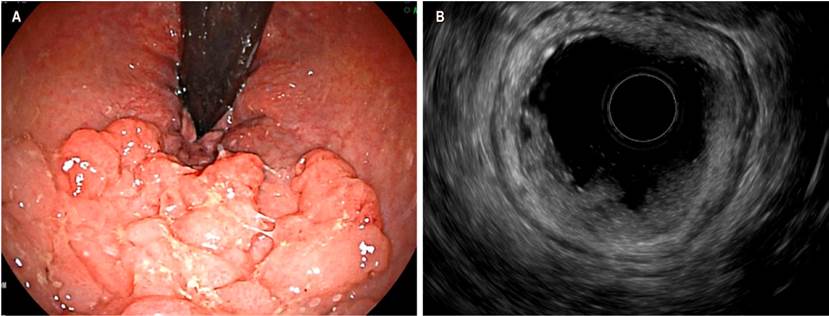

Diagnóstico en tumores colorrectales: pólipos rectales de alto riesgo

En lesiones rectales polipoides no pediculadas mayores a 2 cm de diámetro es importante establecer la probabilidad de invasión a capas profundas para definir la mejor técnica de resección (endoscópica mediante mucosectomía frente a disección endoscópica de la submucosa o técnicas quirúrgicas mínimamente invasivas). Algunos expertos sugieren realizar imágenes complementarias como el USE para definir la técnica de resección ideal en lesiones de alto riesgo como en displasia de alto grado, 0-IIa+c de París, extensión lateral no granular, patrón de Kudo V o mayores a 3 cm 20. Las lesiones con invasión profunda de la submucosa (sm) tienen un riesgo elevado de metástasis ganglionar (sm1 del 2 %, sm2 del 8 % y sm3 del 23 %); por tanto, su manejo debe ser quirúrgico. En este contexto, la RNM tiene un rendimiento variable para definir el grado de invasión de las lesiones polipoides en el recto, particularmente en lesiones polipoides T1 (pT1), en las que la precisión de la profundidad de invasión es variable, desde un 25 % hasta un 98 % 21. En un metaanálisis de 42 estudios con 5309 pacientes, se encontró una sensibilidad y especificidad del USE para la estadificación de lesiones rectales T1 del 88 % y 98 % respectivamente; y del 80 % y 96 %, respectivamente, en lesiones T2. Es por esto que el USE se sugiere como la mejor estrategia diagnóstica para abordar lesiones tempranas (pT1), mientras que la RNM se recomienda para valorar lesiones pT2 o más avanzadas 22.

La Sociedad Europea de Radiología Abdominal y Gastro-intestinal (ESGAR), en su guía para el estudio de neoplasias de recto, sugiere que el USE es el método de elección para la diferenciación y estadificación de lesiones T1 rectales (Figura 5) 23. Se ha descrito que, en las lesiones polipoides del recto, el USE reduce el riesgo de carcinoma no diagnosticado del 21 % al 3 %, al compararse con la endoscopia convencional 24. En este contexto, se ha comenzado a valorar el uso de la elastografía por USE para medir las propiedades elásticas como la dureza del tejido y, de este modo, poder diferenciar entre pólipos benignos y malignos rectales. Un estudio demostró que la elastografía podría diferenciar adenomas benignos de adenocarcinoma invasivo con una sensibilidad del 96 %, especificidad del 86 % y una precisión diagnóstica del 94 % al corroborarse con la patología 25.